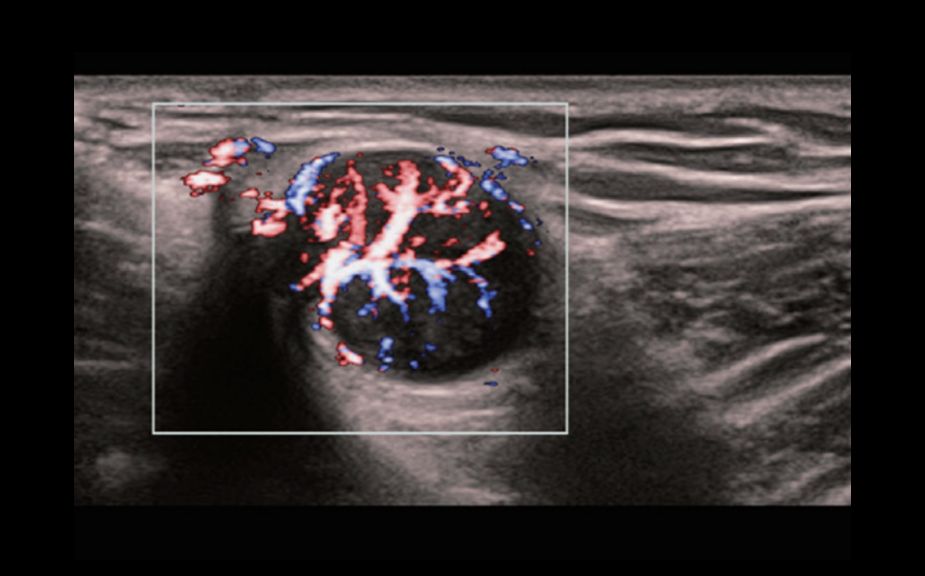

A Novel Approach of Vascular Hemodynamics: V Flow

The color coded vector arrows indicate the velocity magnitude and direction of blood cells. With an ultra-high frame rate, V Flow provides extremely vivid, accurate and angle-independent visualization of complex vascular hemodynamic profiles with comprehensive data information.

V Flow

A Novel Approach of Vascular Hemodynamics: V Flow

The color coded vector arrows indicate the velocity magnitude and direction of blood cells. With an ultra-high frame rate, V Flow provides extremely vivid, accurate and angle-independent visualization of complex vascular hemodynamic profiles with comprehensive data information.

V Flow